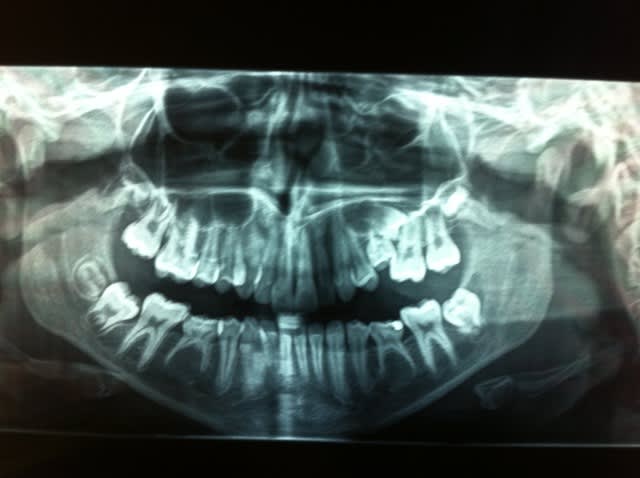

Et celle là, vous en pensez quoi?

La 65 est tombée il y a environ 1 an, puis une 25 s'est pointée et est restée comme ça, pas sur l'arcade.

Ca c'est ce que m'a dit la patiente car je ne l'avais pas vue depuis 1 an 1/2. Mais je crois bien me souvenir qu'il y avait une lacteale et donc nous aurions affaire à une surnumeraire soit imparfaitement constituée soit rhyzalisée par la 5 suivante qui est au dessus (auquel cas la surnumeraire est la plus haute et vice versa)

Bref je pense adresser à une consoeur ortho et un confrere chir pour minivis, reouvrir l'espace, extraire le machin en partie sur l'arcade et prier pour que l'autre 5 continue son evolution et emerge un jour ou qu'on la tracte mais à ce stade tracter me parait tiré par les cheveux.

En bas y'a aussi souci mais ça se reglera plus tard par 2 implants.

En haut quelle conduite à tenir si on ne peut pas amener la 25 en place afin de preserver le max d'os alveolaire en vue d'un implant à venir?

Algi :

Il s'agit d'une réinclusion de la 65. Il y a un problème pour la 25 dont la racine n'est pas développée. Ton patient a 9-10 ans ? Tu peux avulser la 65, rouvrir l'espace et attendre 6-9 mois "pour voir" mais il ne se passera sans doute rien pour la 25 qu'il te faudra alors avulser également. Puis maintien de l'espace et implant en fin de croissance...

Viens de voir le pote chir et je confirme: 65 ingressée par pression de 4 et 6.... la 25 sortira sans doute pas.

J'attends avis ortho pour savoir si on ouvre pour permettre sortie eventuelle de 25 ou si au contraire on ferme et on avance la 6(et à ce moment là on verra pour la 15 et pour les mandibulaires).

Je dirais que pour le haut il faut un CBCT ça vous permettra de voir

- la position des élément dentaire les un par rapport aux autres

- Voir si 25 est ankylosé.

- voir l'état de la 26 ( sur la radio ou pourrait penser qu'elle est atteinte

Dans tout les cas une minivisse me parait inutile je vois trois options

- si 25 est ankylosé ou dans une position impossible on extrait le machin est 25 et on ferme les espaces avec 26 27 .

- Si 26 est intacte extraction de 27 redressement de l'axe de 26 pour faire de la place, traction orthodontique de 25 si besoin pour l'aider a trouver sa place

- Si 26 est abimé ou si le CBCT dis que la mécanique est plus simple extraction de 26, traction ortho de 25 si utile.

Sur ce patient pas de problème la 28 sont en court de formation et viendra compléter l'arcade toute seul comme une grande pas besoin de bracket.

Pour le bas point besoin d'implan ou même d'orthodontie.

Il faut faire des hémisections.

Vous enlever la racine distale de 75 et 85 est la 6 vas se mésialer naturellement, vue que la distance entre les deux racines est faible l'os n'auras pas le temps de fondre et de bloquer les 6 ( se qui se passerait si vous faisiez l'extraction total).

Une fois que l'espace est fermer vous enlever la racine mésiale de chaque coté.

Normalement pas besoin d'ortho, pas besoin d'implant par contre 2 DC 8

Sur ce cout c'est pas mon idée mais une technique reconnue qui a fait l'objet de nombreuse publication.

PS : attention 85 très probablement ankylosée.

Cette 25 a un retard d'évolution, banal et relativement fréquent.

La direction distale ++ qu'on voit sur la pano n'est peut-être pas aussi importante qu'il y paraît, l'image peut-être faussée par son inclinaison vestibulo-linguale.

Conduite à tenir : tu vires la 65 et tu attends que la 25 se redresse en partie.

À ce moment là seulement tu aviseras pour le reste.